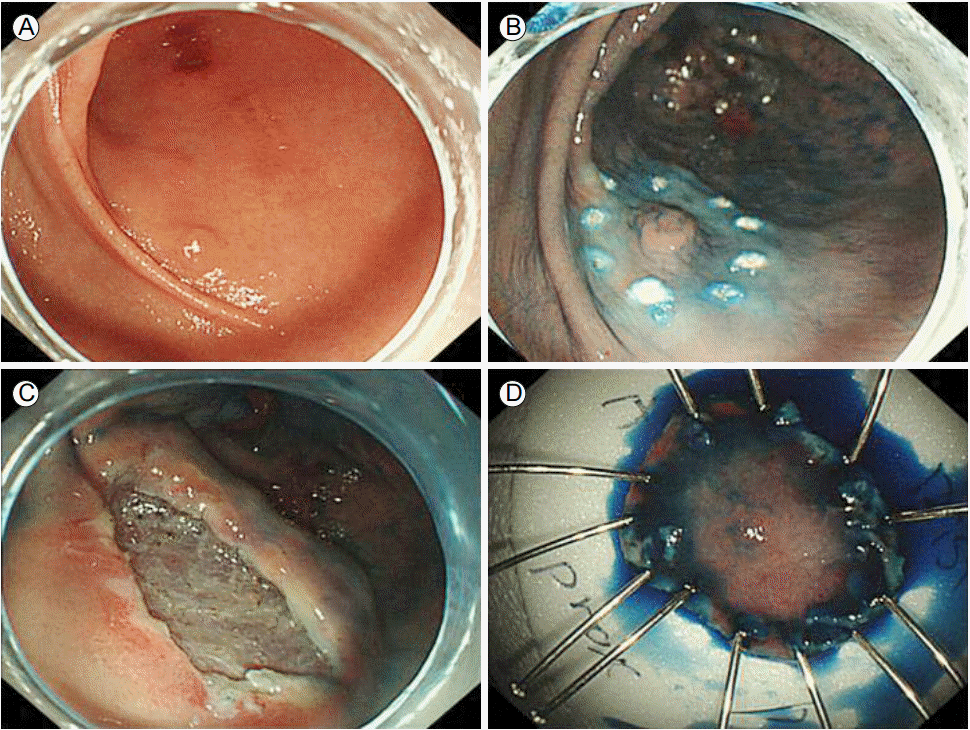

Figure 1.

ESD. (A) Low grade gastric adenoma at the antero-greater curvature side of the proximal antrum. (B) Marking the site. (C) The mucosal bed after ESD was performed. (D) The removed gastric adenoma specimen. ESD, endoscopic submucosal dissection.

환 자: 46세 남자주 소: 위의 저도선종에 대한 내시경절제술현병력: 환자는 위내시경에서 저도선종이 발견되어 내시경 점막하 박리술을 시행받기 위해 입원하였다. 입원 당일 몸쪽 날문방 대만곡부위에 위치한 2 cm 크기의 저도선종에 대해 내시경 점막하 박리술을 시행하였다(Fig. 1). 시술은 표시(marking), 주사(injection), 절개(incision), 박리(dissection)의 순서로 시행하였으며, 시술 후 출혈이나 천공의 징후는 관찰되지 않았다. 시술 후 하루가 경과하여 환자는 섭씨 39℃의 발열 및 상복부 통증을 호소하였다.과거력: 40갑년의 흡연력 외에 특이병력은 없었다.가족력: 부친이 진폐증, 모친이 대장암의 병력을 가지고 있었다.직업력: 건설업진찰 소견: 입원 당시에 특이소견은 관찰되지 않았다. 발열이 시작된 이후에는 급성 병색이었고 의식은 명료하였다. 혈압은 130/70 mmHg, 맥박수는 100회/분, 호흡수 20회/분, 체온 39℃였다. 복부 팽만과 함께 장음은 저하되어 있었으며 상복부 촉진시에 압통와 반발 압통이 있었다.검사실 소견: 내원 당시 온혈구계산에서 혈색소 15.9 g/dL, 백혈구 10,350/mm3 (중성구 68.1%, 림프구 22.9%, 단핵구 5.4%, 호산구 1.5%), 혈소판 353,000/mm3 였으나 발열 이후 백혈구 16,140/mm3 (중성구 88.1%, 림프구 5.4%, 단핵구 5.1%, 호산구 0.6%)으로 증가하였다. 혈액화학 검사에서 C-반응단백질은 3.5 mg/dL에서 시술 후 5.9 mg/dL로 증가하였고 이틀 뒤 36.20 mg/dL까지 증가하였다.방사선 검사: 가슴 X-선에서 천공 및 폐렴 소견은 관찰되지 않았다. 제2병일에 복부 컴퓨터단층촬영을 시행하였으며 중간 위몸통부터 날문부에 걸쳐 미만성 점막하 저감쇠 병변과 전체 위벽의 미만성 부종이 관찰되었다(Fig. 2).진단 및 임상경과: 진단을 위해 제2병일에 위 내시경검사를 시행하였고 내시경 점막하 박리술을 시행한 날문방 대만곡 부위를 포함하여 위벽 전체에 전반적인 부종과 발적이 있었다(Fig. 3). 위 점막에서 고름이나 염증성 삼출물이 관찰되지는 않았으나 내시경으로 공기를 집어넣거나 흡인시 점막에서 쉽게 출혈하였다. 조직 배양을 위해 위점막 조직검사를 시행하였고 이후 위액 배양을 위한 검체 채취를 시도하였으나 흡인시 다량의 출혈이 있어 위액 배양은 시행하지 못하였다.제2병일 발열 발생 시점에 혈액배양 검사를 시행하고 복강내 감염에 준하여 경험적으로 3세대 세팔로스포린(Ceftriaxone 2 g q 24 hrs)과 메트로니다졸(metronidazole 500 mg q 8 hrs)을 투여하였다. 그러나 항생제를 사용하고 있음에도 불구하고 상복부 동통 및 반발통과 압통이 지속되었고, 섭씨 39℃ 이상의 발열이 계속되었다.최종 위점막 조직검사 병리 결과는 급성 염증이었으며 복부 컴퓨터단층촬영 결과와 위 내시경 소견을 종합하여 봉소염성 위염이 가능성이 가장 높다고 생각하였다. 의료 관련 복잡성 복강내 감염시 광범위 항생제의 사용이 권고되는 점을 고려하여[3] 제3병일부터 피페라실린/타조박탐(piperacillin/tazobactam 4/0.5 g q 8 hrs)과 테이코플라닌(teicoplanin 400 mg q 24 hrs)으로 변경하여 투약하였다. 수술적 치료를 고려하였으나 환자와 보호자가 항생제 치료를 유지하면서 경과관찰을 원하였고 항생제 사용 6일째부터 해열되었으며 백혈구증가증의 호전 및 C-반응단백질 수치가 감소하여 수술을 시행하지 않았다(Fig. 4).내시경 점막하 박리술로 절제한 조직의 최종 병리 결과는 위 저도선종이었으며 봉소염성 위염의 소견은 없었다. 환자는 임상경과가 호전되어 경구 항생제인 목시플록사신(moxifloxacin 400 mg)으로 변경하여 퇴원하였으며 2주간 복용 후 중단하였다. 퇴원 두 달 후 외래에서 추적 위 내시경을 시행하였고 내시경 점막하 박리술을 시행했던 부위 궤양 흉터 외 이전 내시경에서 관찰되었던 위 내벽의 발적과 부종은 관찰되지 않았다(Fig. 5).